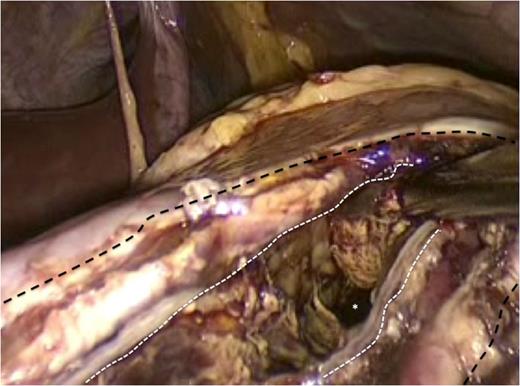

The incision at the anterior stomach wall (outlined by the broken black line) is retracted to allow access to the posterior stomach wall. An endo-GIA stapler has been fired to create a stapled anastomosis (outlined by the broken white line) between the posterior wall of the stomach and the anterior wall of the pancreatic pseudocyst. As a result the pseudocyst is opened widely to facilitate drainage of fiuid and debris into the gastric lumen.